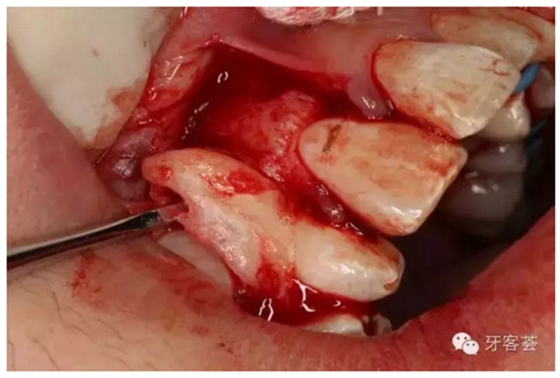

圖8:微創(chuàng)拔除的12牙根畸形嚴(yán)重

圖9:清理12牙槽窩